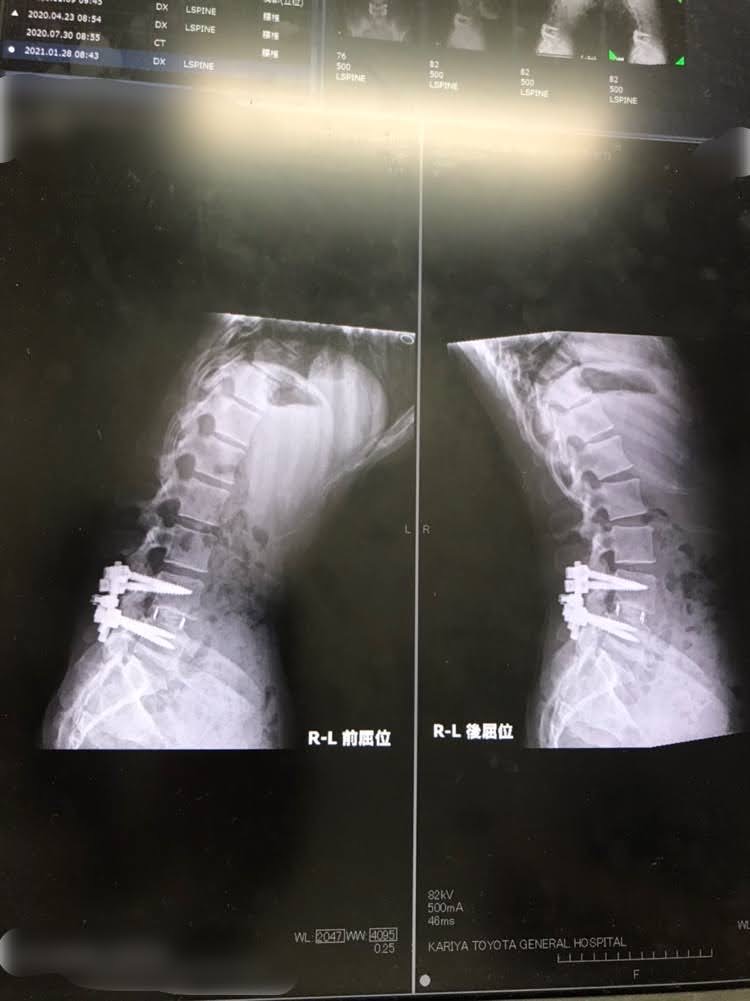

腰椎固定術を受けてあれからもう6年

身体の中にはまだちゃんと金具は入ったままでこれは取り出すことなく最期まで一緒に相棒

全く痛くないのか?

よくそう聞かれますが痛くないとは言えないのが実際のところ。

神経が当たり両下肢に出ていた熱感や激痛は無くなりましたが、腰痛は健在

重たい物を運んだり、長距離を歩いて出かけると腰の筋肉が突っ張るというか硬くなってくる感覚でやっぱりストレッチが必要不可欠。

しかしこんなものが刺さってるけど普通に動ける人間というか、医学はすごい。